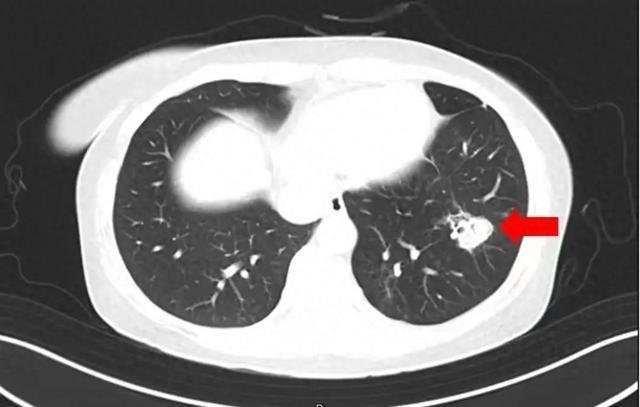

在医生问诊时,沈女士说起了换季整理衣柜的事。她在整理时发现衣柜里长了霉斑,为此还特意把全部衣柜做了清理,但是清理时没有戴口罩。在了解情况后,医生为她做了纤维支气管镜检查及肺泡灌洗液病原体检测,果然发现气道壁上有大量白色菌斑,这就是引起患者高烧、咳嗽的“元凶”——肺曲霉菌病。目前,沈女士经抗真菌及综合支持治疗后病情逐渐稳定,已康复出院。

潮湿环境下,曲霉菌容易滋生,家里洗手间地砖、墙缝等地方都可能是其温床。肺曲霉菌病在临床上分为侵入性肺曲霉菌病、肺曲霉球、气管支气管曲霉病等类型。不同类型的肺曲霉菌病临床表现有所不同。

常见的症状有持续高热不退,服用常规退烧药也难以起到明显效果;咳嗽症状不断加重,还可能伴有胸痛、呼吸困难;咳出的痰液中带有血丝或呈现棕褐色;此外,还可能出现鼻塞、流脓涕、面部疼痛等鼻窦炎症状。严重时可发生呼吸衰竭甚至危及生命。